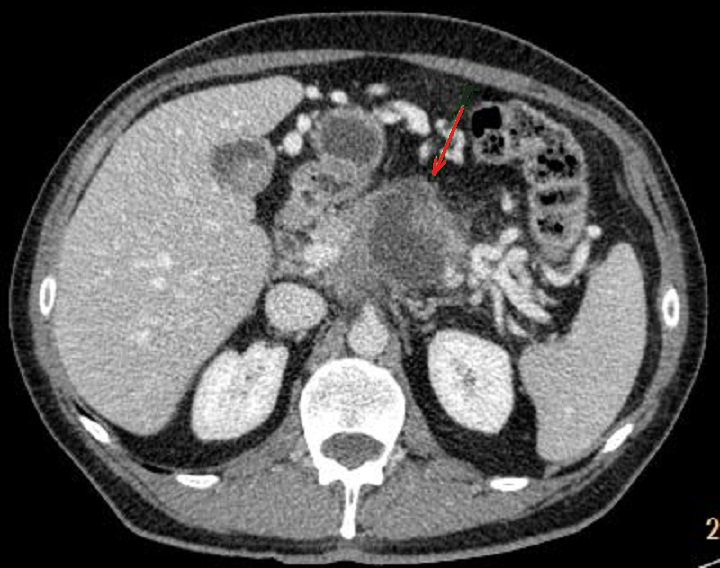

La lesion est volumineuse de

masse tissulaire a hypodense su la TDM , sa bord est

irregulie de mal limite , parfois on voyait image de

bourgeon endocanalaire et image de rehaussement de

contrast de sa paroi . Tous sont peut en respecte de

lesion malignite . Image radiologique TDM plus C+ en

coupe axiale |